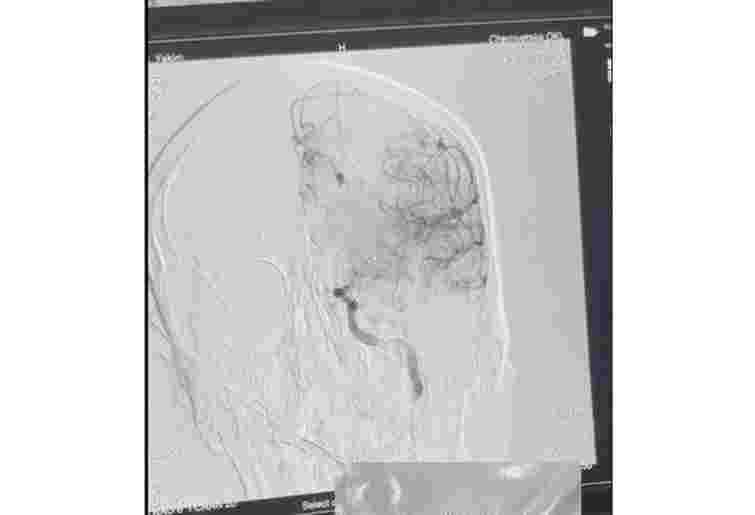

30-річний чоловік потрапив в лікарню через виклик швидкої допомоги. У нього раптово порушилося мовлення, свідомість, зникли відчуття у правих кінцівках. У відділенні невідкладних станів пацієнта оглянув невролог. Під час комп’ютерної томографії головного мозку лікарі виявили велику кількість тромбів у великій судині – лівій внутрішній сонній артерії. Пацієнту терміново провели тромболітичну терапію та ендоваскулярне втручання.

«Під час процедури судину відкрили, забрали тромби, кровопостачання головного мозку відновили. Уже наступного дня пацієнт мав позитивну динаміку, рухи у кінцівках відновилися. Зберігається моторна афазія, з якою він працює разом із логопедом. Прогноз – сприятливий», – зазначила лікарка-неврологиня інсультного відділення Ірина Житарюк.